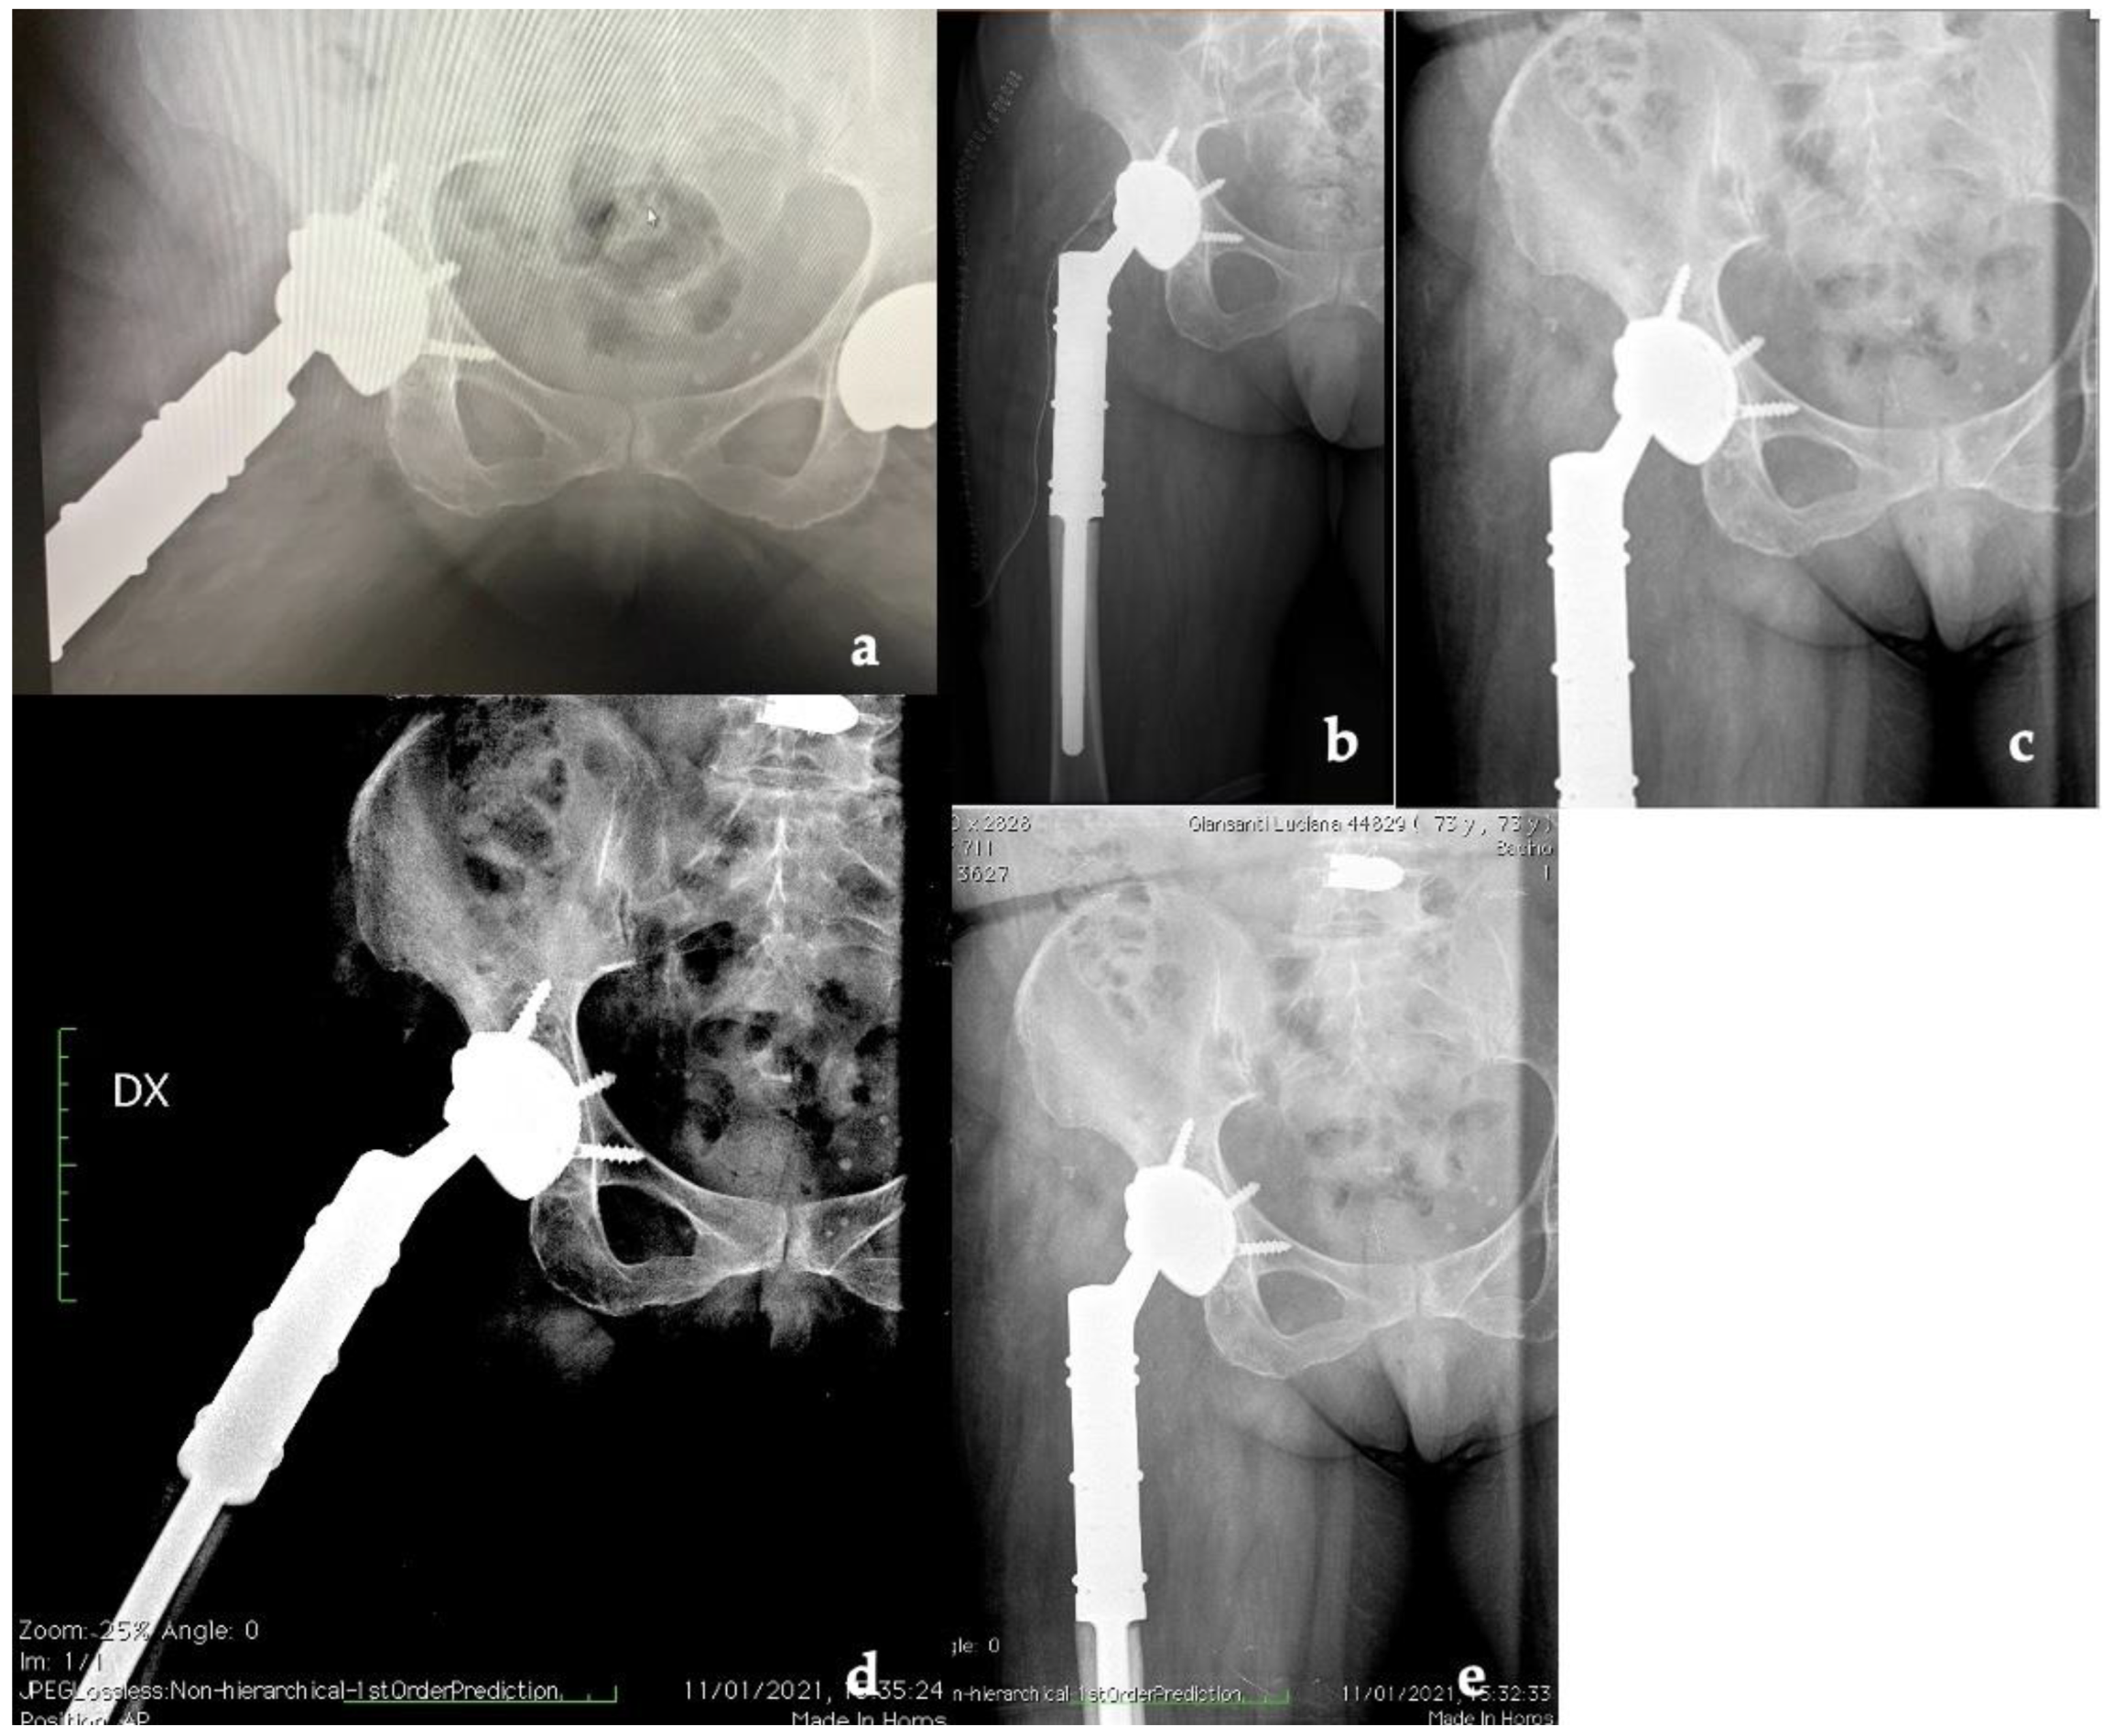

2. Case Report